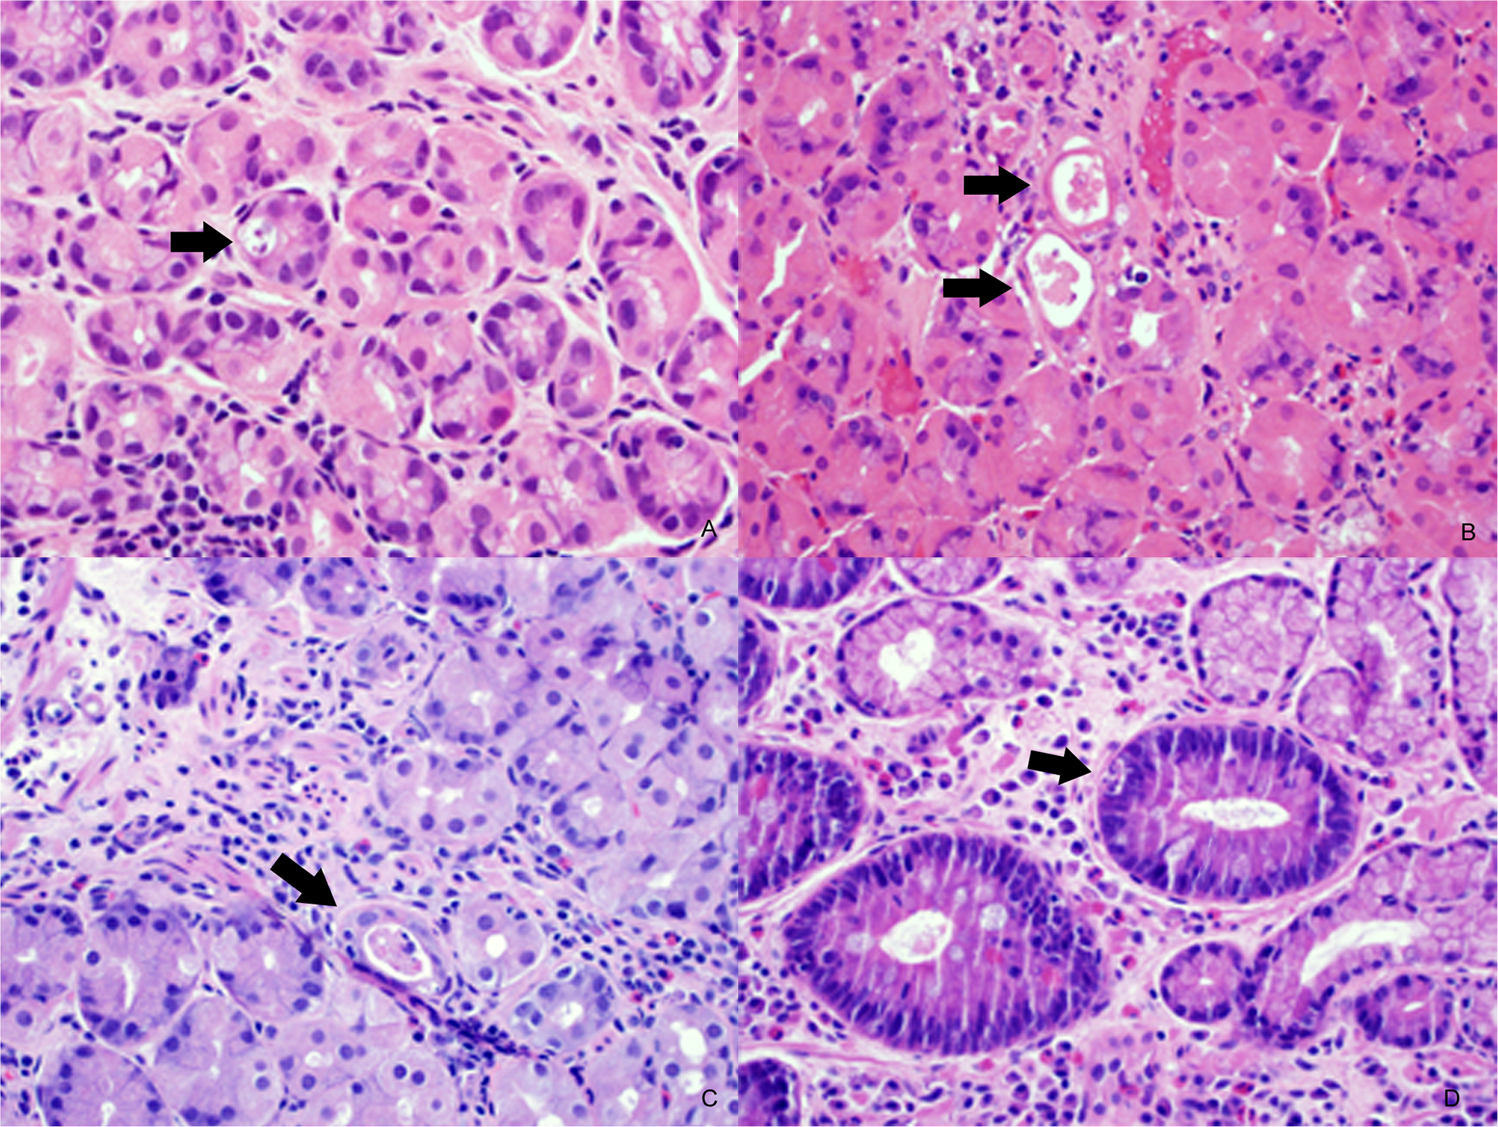

Fig. 1: Gastric biopsy from stem cell transplant patient showing a maximum apoptotic count of 1 apoptotic body/10 contiguous pits (arrow).

This case was reclassified as indeterminate for graft versus host disease (a). Gastric biopsy from stem cell transplant patient with dilated withered pits containing eosinophilic luminal debris (arrows) consistent with gastric pit dropout (b). Control case showing a single gastric pit with luminal debris (arrow). The pit lacks the withered appearance noted in b (c). Control case with intestinal metaplasia showing gastric pit apoptosis (arrow) (d).